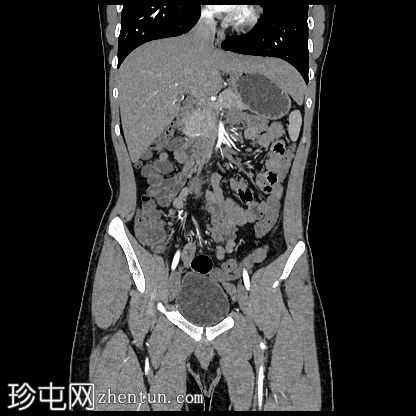

冠状位增强扫描

动脉期

盆腔左侧可见一形态良好的子宫样结构(57 x 17毫米),开口于前列腺尿道。

右侧睾丸位于盆腔右侧,膀胱与直肠之间。大小:56 x 29 毫米。

左侧睾丸位于盆腔中线左侧,膀胱上方,子宫底旁。该结构附着于从左侧腹股沟管延伸出的索状结构上。大小:38 x 22 毫米。

MRI图像显示子宫和睾丸。子宫内膜腔开口于前列腺尿道。

患者有双侧隐睾病史。CT和MRI图像显示发育良好的子宫和两个睾丸,均位于盆腔内。子宫内膜腔开口于前列腺尿道。